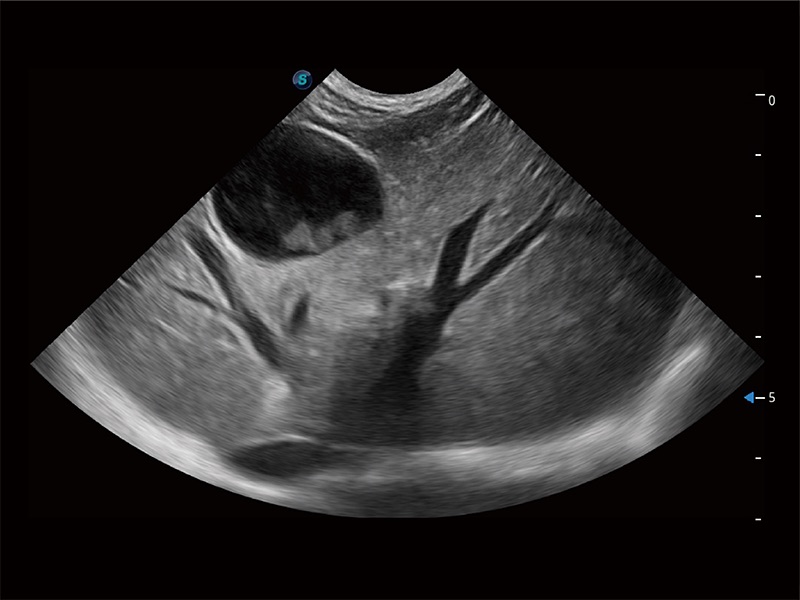

Klinisches Vertrauen verlangt hohe Leistung und fortschrittliche Werkzeuge. ProPet wurde für abdominelle und oberflächliche Untersuchungen mit fortschrittlichen Werkzeugen entwickelt, die Tierärzten in der täglichen klinischen Praxis helfen wie nie zuvor.

Ausgestattet mit dem gesamten Sortiment an Phased-Array-Schallköpfen von SonoScape (S1-5, 7P-A, 8P1), hochentwickelter Verarbeitungstechnologie und modernsten kardiologischen Tools bietet die ProPet-Serie Tierärzten eine umfassende ABklärung der Herz- und Myokardfunktionen.